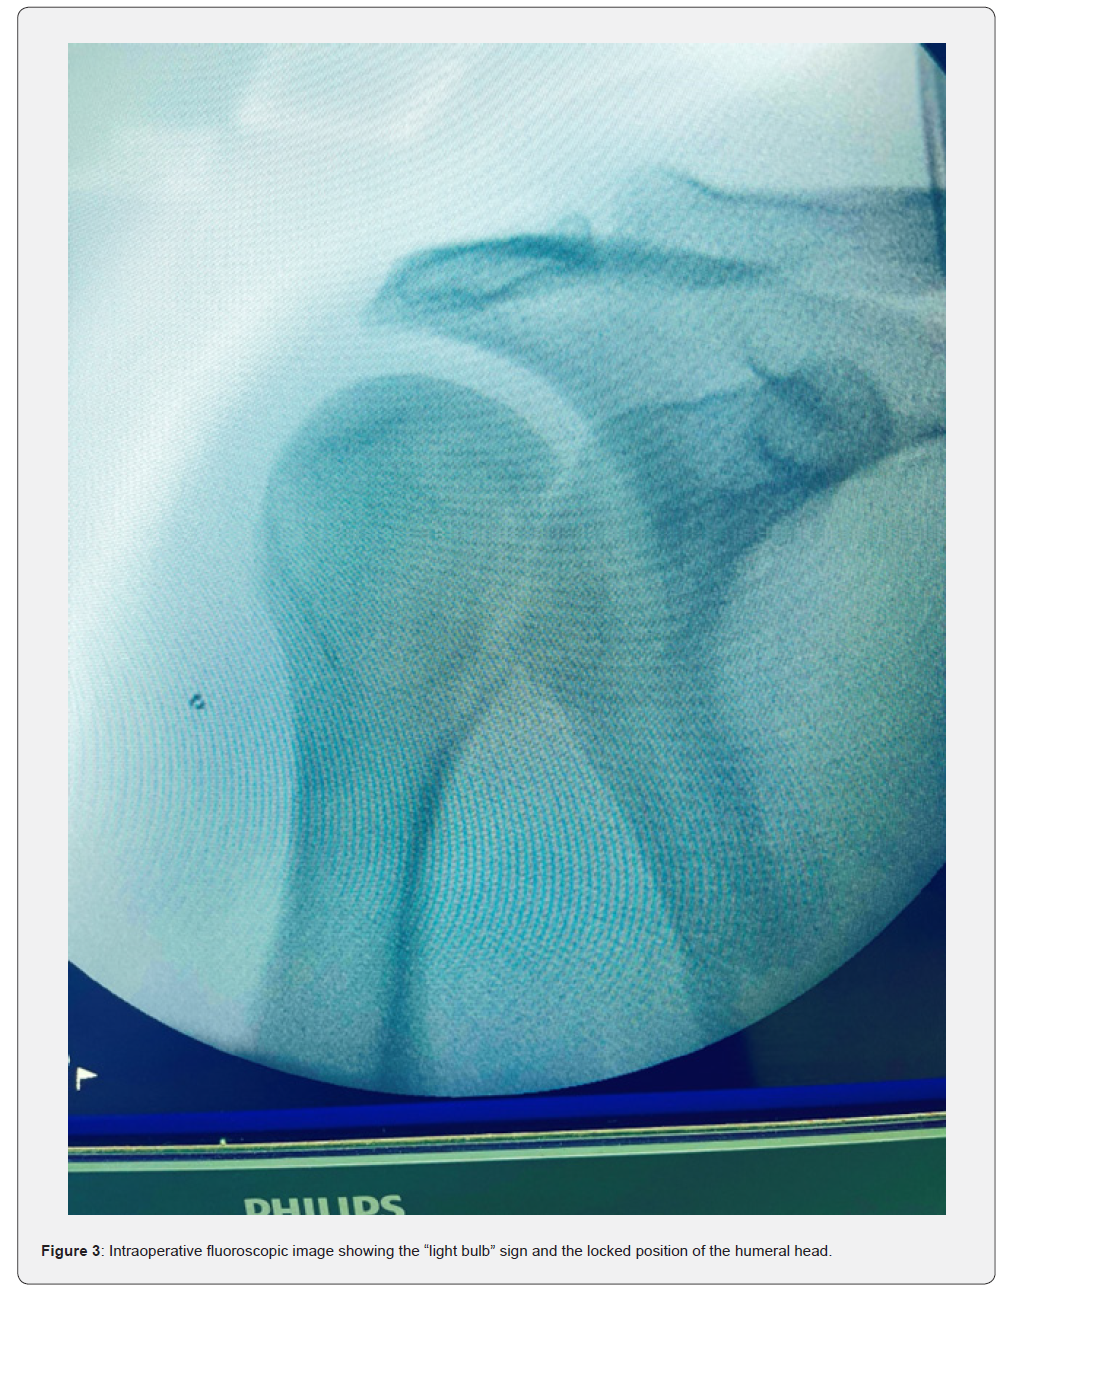

Intraoperative fluoroscopic images further delineated the light bulb sign and locked position of the humeral head (Figure 3).